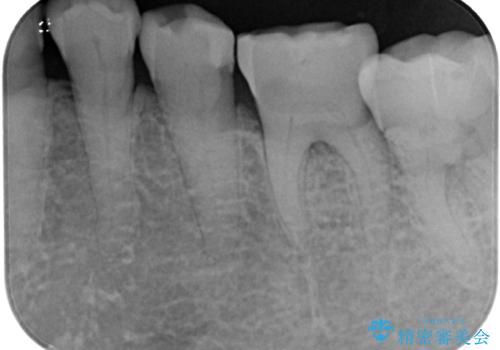

- 奥歯がたまにしみることがあるとのことで来院された患者様です。

特に問題となるような歯髄症状はなく、装着されている詰め物の境目がしみているような状態でした。

相談の上、フルジルコニアクラウンにて補綴治療を行うこととしました。